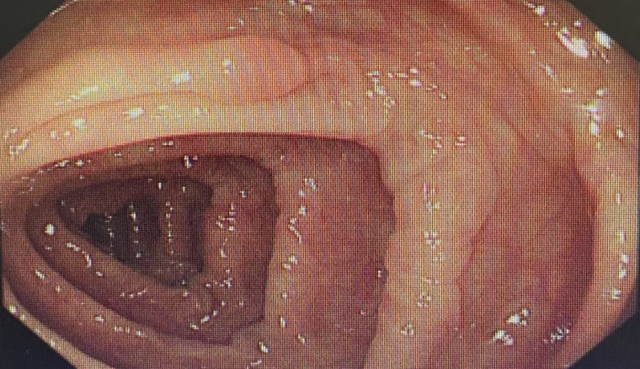

在我院消化康复科近期的肠镜检查中,结肠息肉的检出率引起了医护团队的关注。这些生长在肠道黏膜表面的赘生物,在医学上被明确认定为结直肠癌最重要的癌前病变之一。其中,腺瘤性息肉具有明确的恶变倾向,研究显示,相当比例的结直肠癌是由此类息肉经历“息肉—腺瘤—癌变”的缓慢过程演变而来。因此,在息肉阶段早期识别并予以切除,是阻断癌变链条、预防肠癌发生的关键措施。

很多人往往认为,身体没有不适就等于健康。58岁的李女士(化名)也曾这样想,平时她从未感到腹部疼痛或腹胀,排便也一直正常。然而,在一次常规肠镜检查中,医生却发现她的结肠壁上分布着数枚息肉,最大直径约2厘米,小的仅如米粒大小(约0.3厘米)。这些“肠道多余物”本身可能不引起任何症状,但其潜在危险不容小觑——它们正是结直肠癌最重要的“前奏”。

肠镜不可替代:肠镜是目前结直肠癌筛查的金标准。它不仅能清晰观察整个结肠黏膜,发现毫米级的微小病变,还能同时进行活检或切除,实现“诊”与“治”一体。刘先生的早癌病灶,正是通过肠镜被及时发现并根治的。